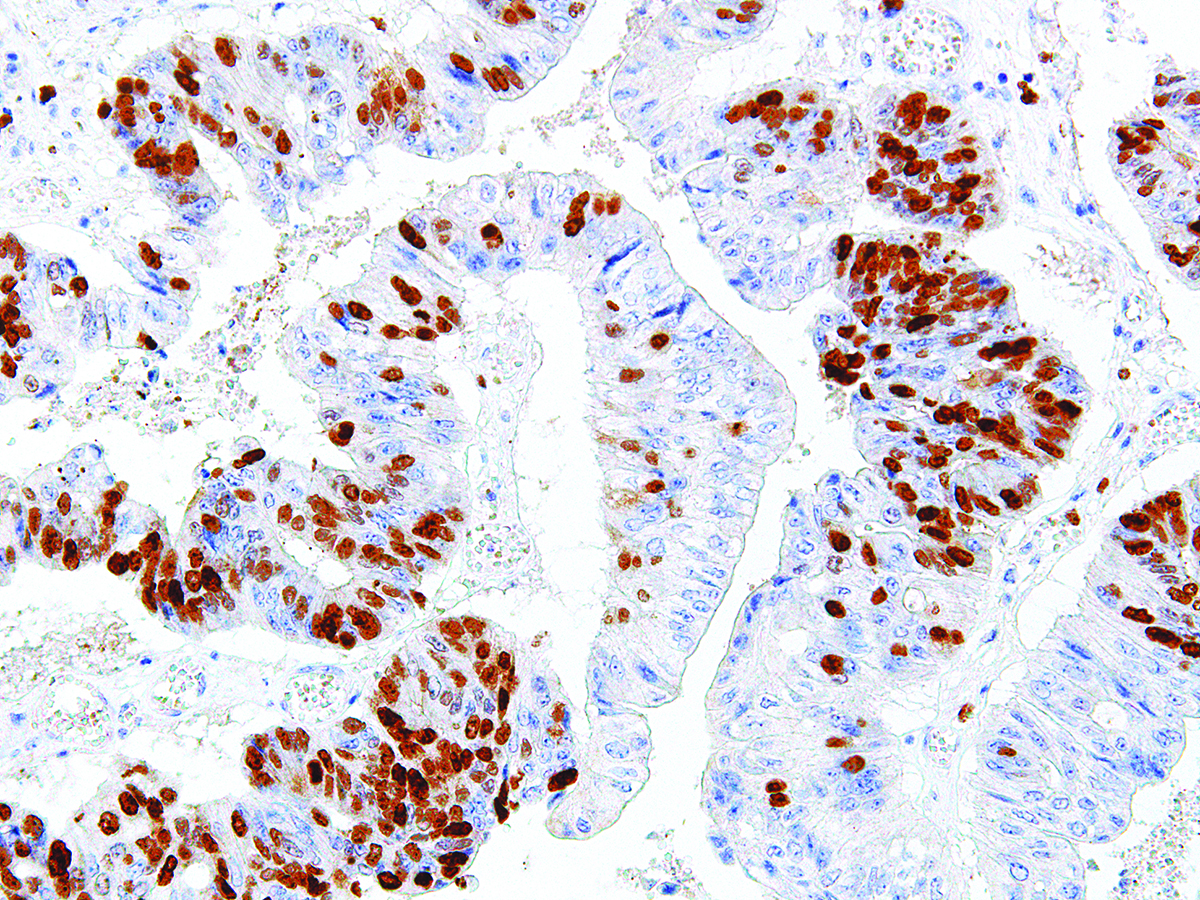

[Genomeme] Survivin

| Clone | IHC668 |

| Source | Mouse Monoclonal |

| Positive Control | Lymphoma |

| Dilution Range | 1:100 - 1:400 |

Survivin is an apoptosis inhibitor that is nearly undetectable in terminally differentiated cells, but found in most tumors including renal cell carcinoma, ovarian carcinoma, hepatocellular carcinoma, prostate carcinoma and breast carcinoma. Survivin expression is linked to tumor progression, but not patient survival.